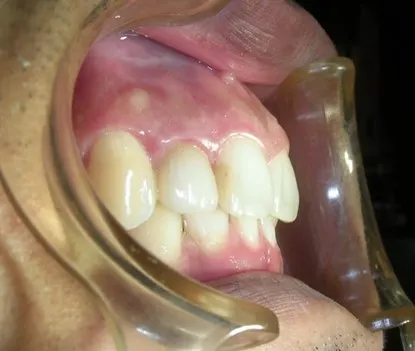

<<三年又三個月後的今天 陳先生回診>>

這顆Cap-Lock 依然這麼美觀而自然

牙齦的部份也沒有發炎或者變色

乍看之下,還真忘了它其實是顆我幫他做的Cap-Lock假牙,倒是遠心用樹脂填補的部份,三年多下來已經變色了!